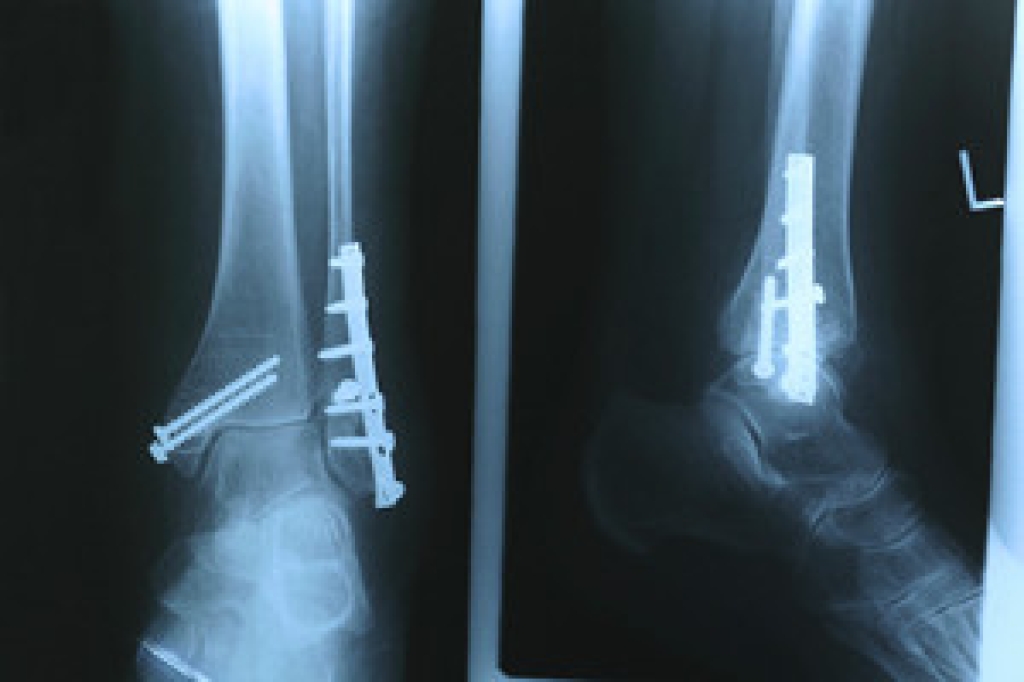

Rheumatoid Arthritis (RA) is an autoimmune disorder in which the body’s own immune system attacks the membranes surrounding the joints. Inflammation of the lining and eventually the destruction of the joint’s cartilage and bone occur, causing severe pain and immobility.

- Joint shift and deformation

Quick diagnosis of RA in the feet is important so that the podiatrist can treat the area effectively. Your doctor will ask you about your medical history, occupation, and lifestyle to determine the origin of the condition. Rheumatoid Factor tests help to determine if someone is affected by the disease.